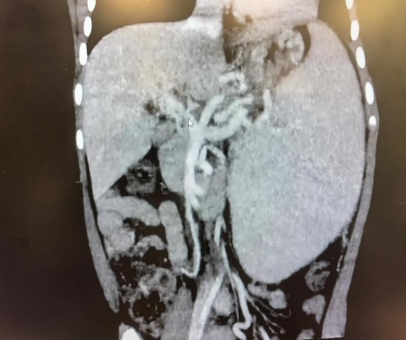

術(shù)前CT血管影像評估

(圖源:四川大學(xué)華西醫(yī)院)

Preoperative CT angiography evaluation

(Credit: West China Hospital of Sichuan University)

2026年2月26日,阿瓦勒攜妻女抵達(dá)成都。3月3日,阿菲亞入院,小兒外科為她進(jìn)行了全面檢查:影像學(xué)檢查顯示,阿菲亞門靜脈主干海綿樣變性,脾臟重度增大,食管胃底靜脈重度曲張,隨時可能大出血危及生命。

On 26 February 2026, Abdul Awal, his wife, and little Afiyah arrived in Chengdu. By 3 March, Afiyahwas admitted to the hospital, where the pediatric team conducted a comprehensive examination of her. The medical challenge was immense: Afiyah suffered from severe splenomegaly (an enlarged spleen), esophagogastric varices, and a portal vein trunk that was both malformed and narrowed. She was at constant risk of a massive, potentially fatal haemorrhage.